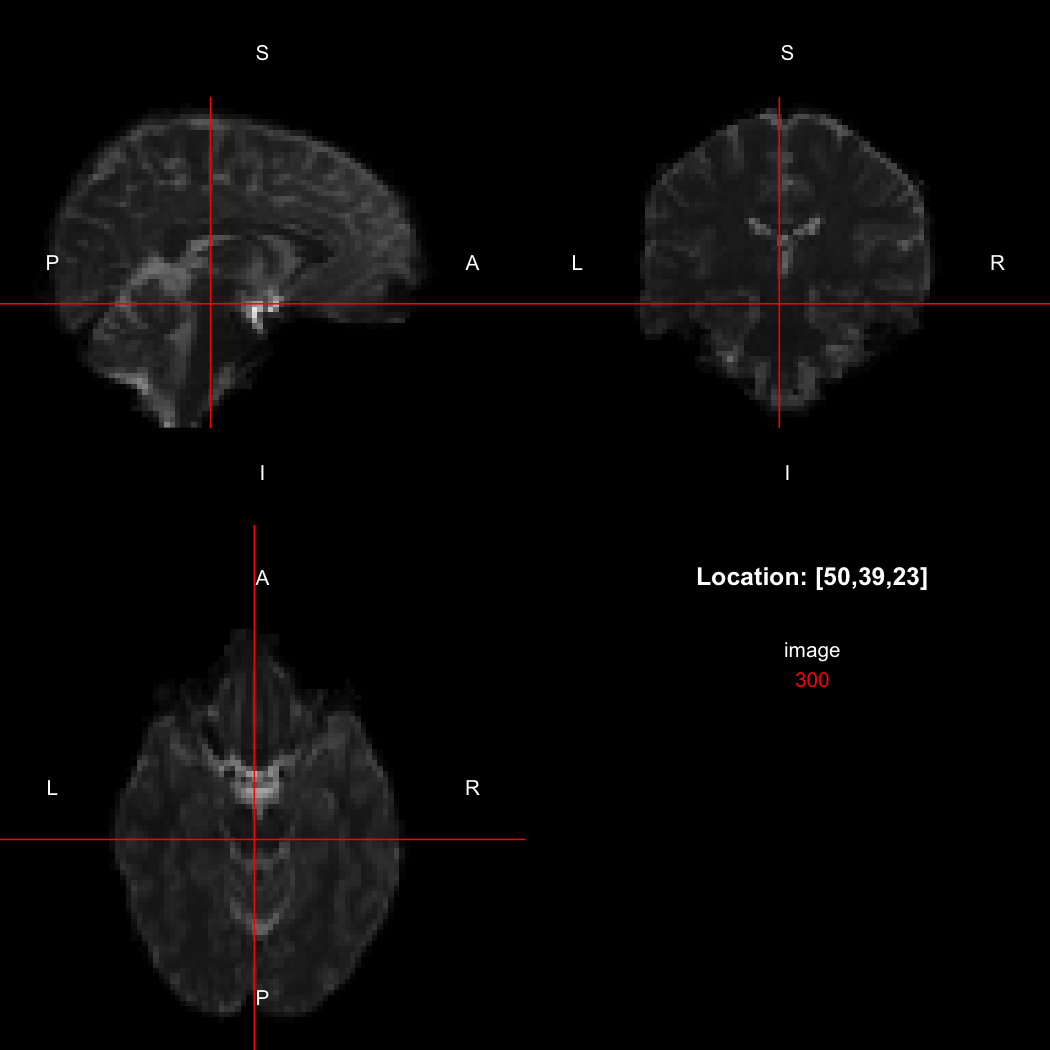

The package contains a basic image viewer, which can be used interactively or noninteractively to examine 2D or 3D images.

view(image)

By default, the viewer shows labels indicating image orientation, crosshairs pinpointing

the currently selected location, the numerical indices of the current

location, and the value of the image at that location. Options allow

each of these to be turned off, for the content of the bottom-right

panel to be customised entirely, for the colour scale to be changed, and

for additional images to be layered on top of the base image. See

?view for details.

## [1] "LAS"So, here, “LAS” means that the positive x-axis points left, the positive y-axis anterior and the positive z-axis superior. This is the so-called “radiological” orientation convention, and can be requested when viewing images for those who are used to it:

view(image, radiological=TRUE)

Notice the left (L) and right (R) labels, relative to the view shown

above. Setting the radiologicalView option to

TRUE will make this the default for all future views.